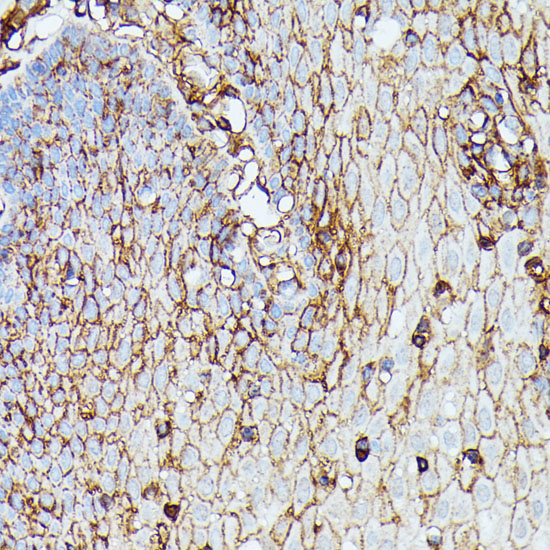

Immunohistochemistry of paraffin-embedded rat spleen using HLA-B at dilution of 1:100 (40x lens).

Immunohistochemistry of paraffin-embedded human esophageal using HLA-B at dilution of 1:100 (40x lens).

Immunohistochemistry of paraffin-embedded mouse spleen using HLA-B at dilution of 1:100 (40x lens).